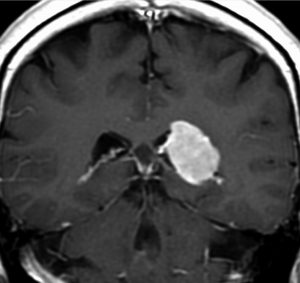

側脳室三角部髄膜腫 lateral ventricle (trigon) meningioma

50歳くらいの女性に偶然発見された三角部髄膜腫です。この部位はとても巨大にならないと症状が出ないので,しばらく様子を見ることにしました。

5年後です。増大傾向が止まりません。大きくなると手術リスクがすごく高くなるので,開頭手術で摘出することにしました。

右側は,手術翌日のMRIです。頭頂部の皮質経由で腫瘍は全摘出できています。専門的には,頭頂部経皮質到達法 parietal transcortical approach, high-parietal approachといいます。この患者さんは幸い頭頂葉症状は全く出ませんでした。でも巨大な三角部髄膜腫になると頭頂葉症候が手術後遺症として残ることがあります。でも慎重な手術をすれば日常生活に大きな支障となることはほとんどないでしょう。